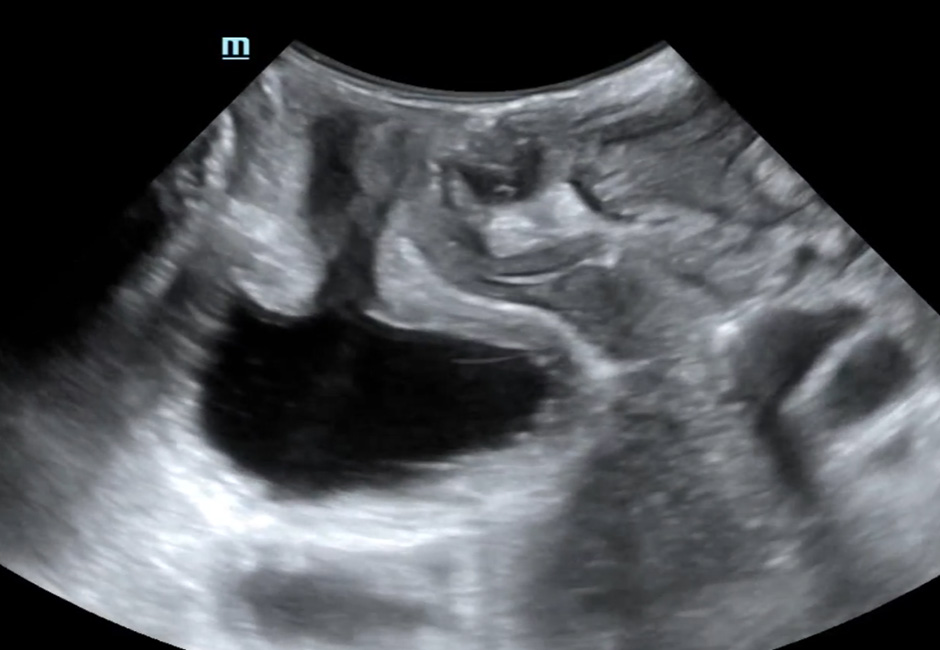

Green Classification of Cystocele-type III

Uterine Prolapse

Rectocele

Cystocele-Bladder neck funneling-Rectocele

Cystocele-Uterine prolapse-Enterocele